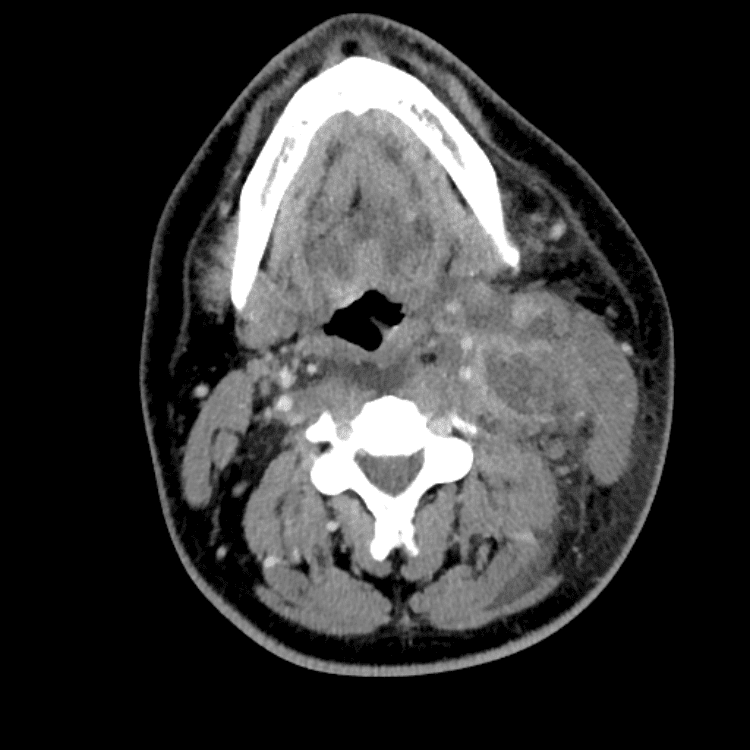

Head and Neck

Practice

Simulates call by including subtle or difficult cases and some normals.

27 cases